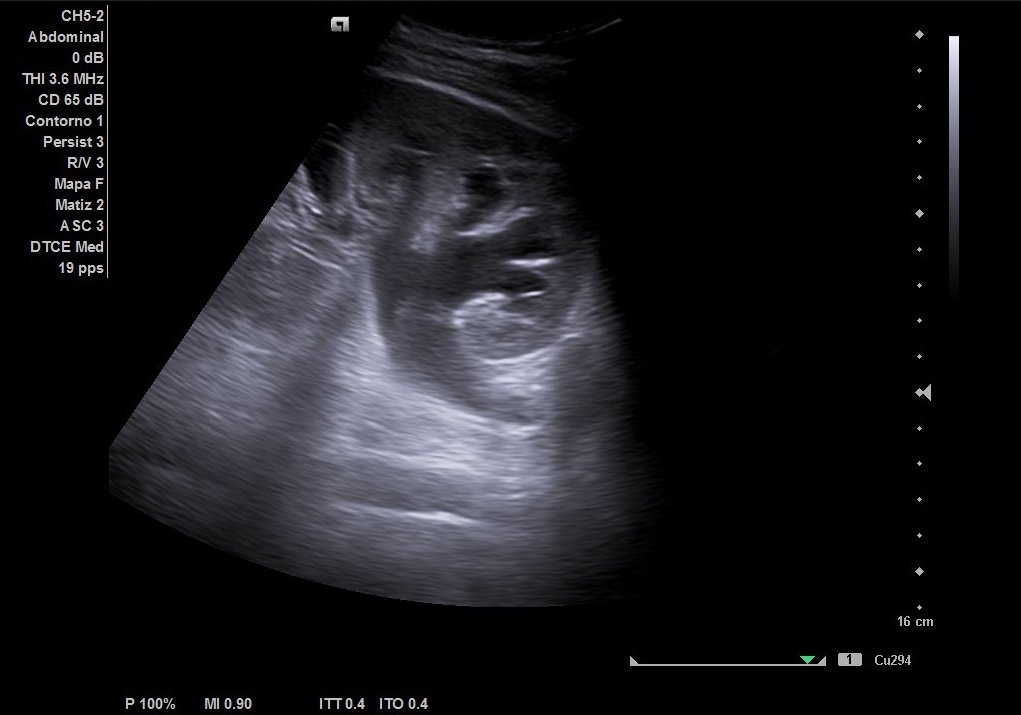

Hallazgos ecográficos

Como hallazgos, observamos dilatación del uréter proximal con hidronefrosis grado II-III. Sin visualización de imágenes compatible con litiasis. Riñón derecho de tamaño y ecoestructura normal sin dilatación de vía excretora. Vejiga vacía y ausencia de liquido libre.

De este modo, la ecografía puede resultar una herramienta clave en el manejo de Urgencias en Atención Primaria. Desde el punto de vista ecográfico, nos resulta fundamental en casos como el de nuestro paciente, conocer si hay una causa obstructiva que desencadene el dolor y produzca dilatación de la vía excretora, para derivar a Urgencias Hospitalarias.